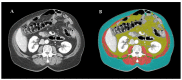

Sarcopenia is common in metastatic colorectal cancer (mCRC), increases the risk of treatment-related toxicity and reduces survival. Trifluridine/tipiracil (TT) chemotherapy significantly improved survival in refractory mCRC patients, but the prognostic and predictive role of pretherapeutic sarcopenia and variation in the skeletal muscle index (SMI) during this treatment has not been investigated so far. In this retrospective, observational study, clinical data on mCRC patients treated with TT at six cancer centres in Poland were collected. Computed tomography (CT) scans acquired at the time of initiation of TT (CT1) and on the first restaging (CT2), were evaluated. SMI was assessed based on the skeletal muscle area (SMA) at the level of the third lumbar vertebra. Progression-free survival (PFS) and overall survival (OS) were calculated from the treatment start. Neither initial sarcopenia nor ≥5% skeletal mass loss (SML) between CT1 and CT2 had a significant effect on PFS in treated patients (p = 0.5526 and p = 0.1092, respectively). In the multivariate analysis, reduced OS was found in patients with ≥5% SML (HR: 2.03 (1.11-3.72), p = 0.0039). We describe the prognostic role of sarcopenia beyond second line treatment and analyze other factors, such as performance status, tumor histological differentiation or carcinoembryonic antigen level that could predict TT treatment response.